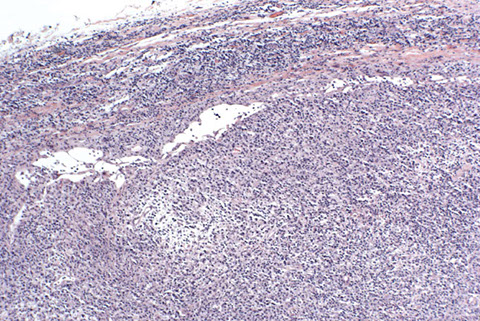

Micro: LN c diffuse nodal involvement showing pseudofollicular architecture (no true mantle zone) c large pale prolif centers c prolymphocytes (>11%; sm to med size cells c clumped chromatin and small nucleoli), paraimmunoblasts (larger, c round to oval nuclei, central red nucleoli)

CLL/SLL can have a perifollicular and/or follicular growth pattern

Smudge cells seen in PB with small lymphs c clumped chromatin and round nuclei

- lots of prolymphocytes in PB = poor px (>55% prolymphs = B-cell prolymphocytic leukemia (B-PLL)

- can see prolif of small, mature lymphs c multiple prolif centers / pseudofollicles

CLL pseudofollicle (proliferation center). Little lymphocytes with small cytoplasm on the left. On the right, paraimmunoblasts are larger, with a little more cytoplasm, with prolymphocytes (black arrow)showing dispersed chromatin, and the red arrow to paraimmunoblasts with prominent central nucleolus (called "paraimmunoblasts" because typically smaller than B-type immunoblasts).

LASOP lecture Dr Reichard, 1/18/2020